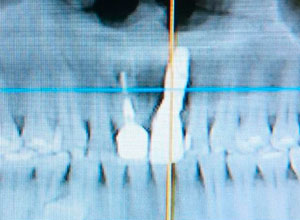

La paciente inconforme con los resultados nos visita, realizamos estudios radiográficos y tomográficos, encontrando que se perdió hueso verticalmente en el implante.

Decidimos hacer una corticotomia alveolar, dejando tejidos blandos en su lugar y cambiar la corona de cerámica por una corona de acrílico para cementar bien los brackets y poder empezar con la distracción.

Después de la corticotomia dejamos un tiempo de siete días para que se organizaran las células tisulares.

Se empezó a hacer la distracción, primero con un arco recto y posteriormente con elásticos haciendo el recorte con el borde incisal conforme se va bajando el implante con el bloque óseo.